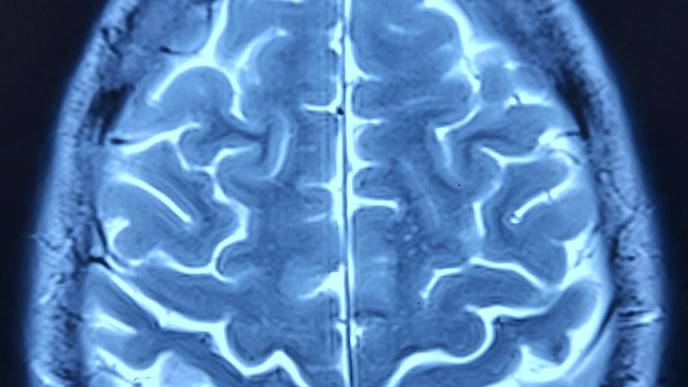

The webinar will highlight cutting-edge research from Dr. Yip’s Yale Imaging and Psychopharmacology Lab. Her work combines machine learning with network neuroscience to assess brain processes related to addiction. By identifying specific brain networks that predict individual differences in substance use outcomes—such as opioid and cocaine use in adults and alcohol use in youth—this research offers new pathways for personalized treatment approaches. Attendees will gain insights into how these techniques can help translate laboratory findings into real-world clinical solutions, a key challenge in psychiatry today.